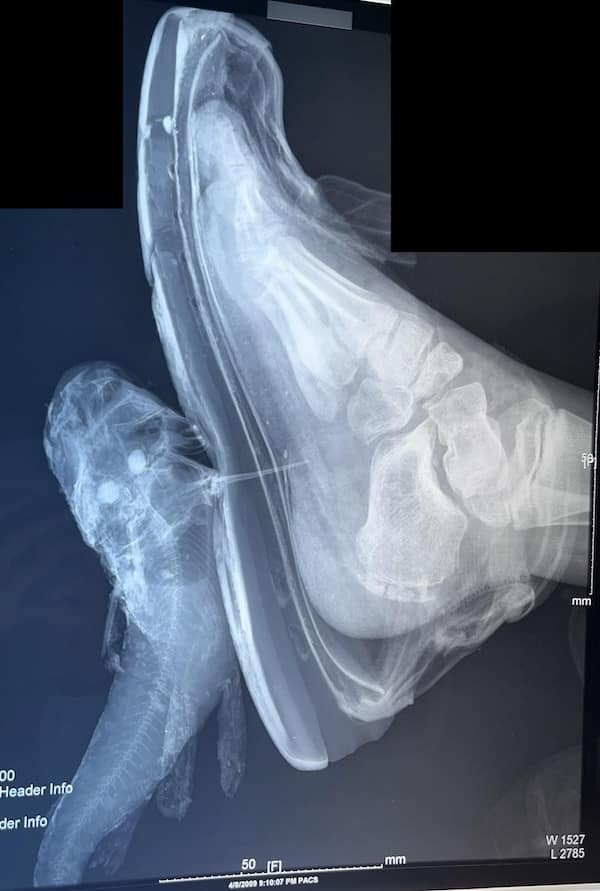

I used to think that nothing could surprise me anymore—until I stumbled upon some weird x-ray photos that made me reconsider my stance on human ingenuity (or lack thereof). Apparently, some people have a knack for getting objects lodged where they absolutely shouldn’t be. If you’ve ever wondered how not to use everyday items, these images might provide some unintended guidance.

This collection showcases 31 bizarre x-ray images that defy logic and anatomy textbooks alike. Each photo reveals unexpected objects making cameo appearances inside the human body, turning medical imaging into a gallery of the absurd. From common household items inexplicably found in unusual places to anomalies that would leave even seasoned doctors scratching their heads, these images offer a perplexing glimpse into the more “creative” side of medical emergencies. They highlight the intersection of curiosity, misadventure, and perhaps a dash of poor decision-making, all captured through the lens of radiology.